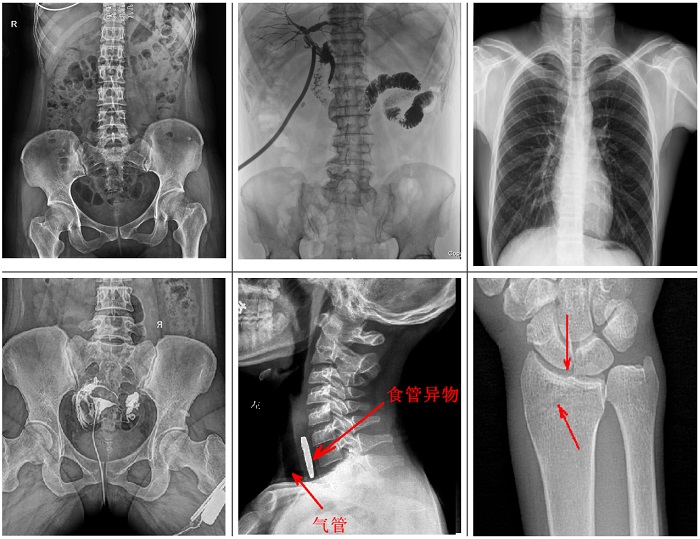

不同于傳統(tǒng)靜態(tài)懸吊DR,普利德多功能懸吊動(dòng)態(tài)DR搭載動(dòng)態(tài)平板探測器,同時(shí)具備數(shù)字?jǐn)z影、透視、造影功能,全脊柱、全下肢圖像拼接等功能,臨床應(yīng)用更加廣泛,可通過動(dòng)態(tài)實(shí)時(shí)連續(xù)成像,對(duì)于重疊部位病灶或者易被遮擋的病灶進(jìn)行多角度動(dòng)態(tài)觀察,極大的提升篩查診斷的精準(zhǔn)性。

可供各級(jí)醫(yī)院進(jìn)行人體頭部、頸部、胸部、腹部、腰椎、四肢等部位的臥位、正位、側(cè)位、斜位的數(shù)字化攝影、透視及造影檢查;適用于各級(jí)醫(yī)院臨床各個(gè)科室,滿足放射科、體檢中心、影像中心、內(nèi)科、外科 、急診科、骨科、創(chuàng)傷科、消化科等科室的多種臨床檢查需求。